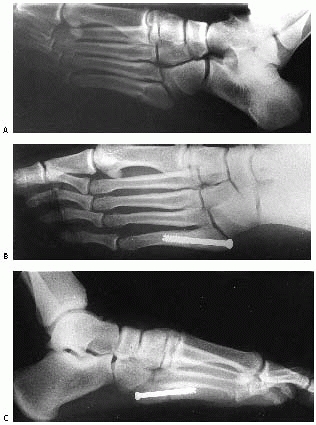

force (Fig. 27-26 ).172,173

foot, usually secondary to a falling object, or indirect, where there